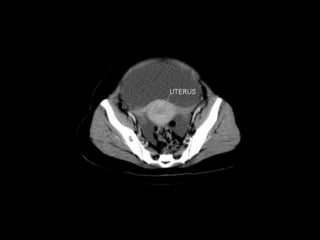

Urinary Bladder:

 The urinary bladder is covered superiorly by peritoneum.

 The body is a hollow muscular cavity.

 The neck is continuous with the urethra.

 The trigone is a smooth triangular area of mucosa located

internally at the base of the bladder.

 The base of the triangle is superior and bounded by the two

openings of the ureters.

 The apex of the trigone points inferiorly and is the opening for

the urethra.

CT cross sectional

anatomy.